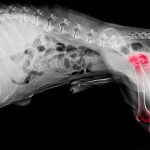

Le cancer chez le chien

Le cancer du poumon chez le chien

Le cancer du foie chez le chien

L’hémangiosarcome chez le chien

Les tumeurs de la rate chez le chien

Le cancer des os chez le chien

Le lymphome chez le chien